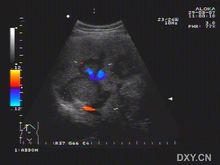

B超:肝內單發或多髮結節,可為低回聲、強回聲或不均勻回聲,腫塊內部回聲為高回聲,周圍包繞寬0.5~1cm的低回聲聲暈,偶爾有的高回聲中央可有少許低回聲區或無回聲區,為癌腫中心出血、壞死所致,此即為“牛眼征”,或稱“靶環征”。CT增強示:腫瘤強化,境界清楚,中央密度多低於周圍部,腫瘤邊緣可顯示環形不規則強化,部分可見“牛眼征”,表現為病灶中心為低密度,邊緣為高密度強化,最外層密度又低於肝實質。

該徵象被認為是轉移性肝癌典型影像表現,可見於任何轉移型肝癌,但多見於腺癌的肝轉移。

超聲“牛眼征”